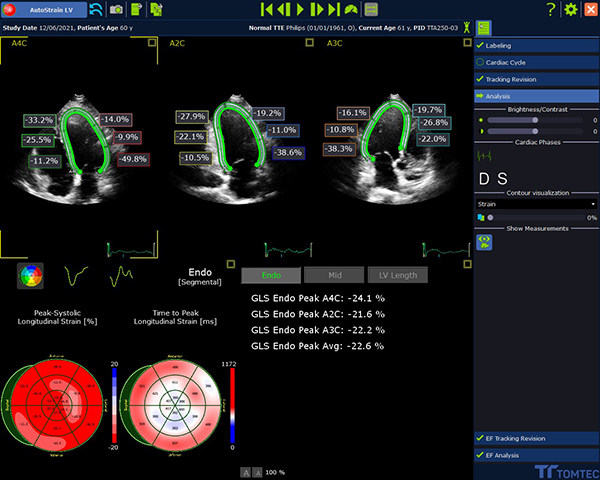

・Strain解析等もAIの導入で手軽にできる心エコー画像解析システム

TOMTEC Imaging Systems社製「TOMTEC-ARENA」